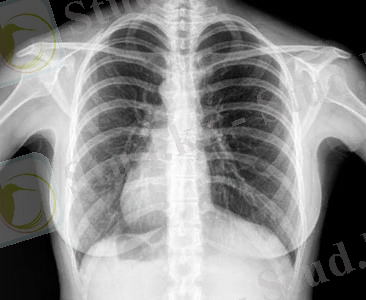

Сурет - 1. Ультрадыбыстық диагностикалық жүйесі

Ультрадыбысты диагностика.

Ультрадыбысты диагностика - диагнозды қою және емдеу тактикасын таңдау барысында өте маңызды дәйек. Бұл жоғары деңгейде ақпарат беретін және еш қауіпсіз түрде зерттеу әдісі. Доплерографиялық зерттеуге қосымша ретінде дәрігерге едәуір нақтырақ диагноз қоюға немесе патологияны жіберіп алмауға мүмкіндік береді.

Соңғы жылдары ультрадыбысты диагностика келесі техникалық жетістіктердің арқасында біршама айтарлықтай прогреске жетті: трансректальді және трансвагиналды датчиктерді, Доплер эффектісін (түрлі-түсті, энергетикалық, спектральді доплерография) пайдаланатын әдістемелерді қолдану. В-режимінде және оның модификацияларында (екінші гармоника, В- flow) аспаптардың рұқсат ету қабілеттілігін арттыруға қол жеткізе алдық.

Ультрадыбыстық диагностика

Қазіргі кезде медицинада ультрадыбыстық диагностика (эхолокация) кеңінен қолданылады. Осы әдіс арқылы адам ағзасының ішінде пайда болған түрліше бітімдердің (ісік, жалқаяқ - ірің, бауыр мен бүйректегі тастар және т. б. ) пішінін, өлшемдерін және орнын дәл анықтауға болады. Сонымен қатар ультрадыбыстық эхолокация хирургияда, онкологияда, гинекологияда және т. б. кеңінен қолданылады.

Ультрадыбыс акустикалық кедергілері әртүрлі екі ортаның шекарасынан шағылады. Мысалы, бұлшық ет - сүйек қабығы - сүйектің шекараларында, ағзаның қуыс беттерінде ультрадыбыс жақсы шағылады. Сондықтан адам ағзасындағытығыздығы әртүрлі бітімдеріанықтауға болады. Осы әдісті ультрадыбыстық локация дейді.

УД-локация қондырғысы генератордан, УД-импульс тарататын датчиктен Д және шағылған дыбысты қабылдаушыдан және электрондық осцилографтан тұрады. Қабылдаушы қабылдаған импульстарының айырмасы нұсқаның жатқан тереңдігін көрсетеді, ал датчиктің қозғалысы нұсқаның пішінін көрсетеді.

Осыған негізделген көптеген диагностикалық тәсілдер бар. Мысалы: эхоэнцефалография - мидағы ісікті және мидың қабынуын анықтайтын тәсіл, УД-кардиография - жүректің өлшемдерін анықтау, офтальмологияда - көз ортасының бітімін анықтау және т. с. с. УД-локациямен қатар диагностика мақсатында УД-ның жұтылу процесін зерттеуде қолданылады. Акустикалық қасиеті әр түрлі екі ортаның шекарасында ультрадыбыс жұтылады.